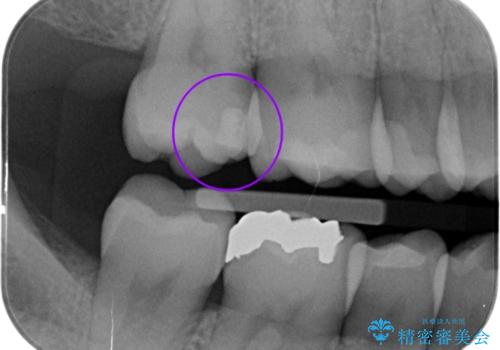

歯と歯の間の虫歯の治療。(コンタクトカリエス)

- メンテナンスで歯と歯の間に虫歯があったので拡大鏡下で虫歯を全て取り除き、e-maxインレーにて治療を行いました。

歯と歯の間は虫歯になるリスクが高い場所なので毎日のフロスをお勧めします。